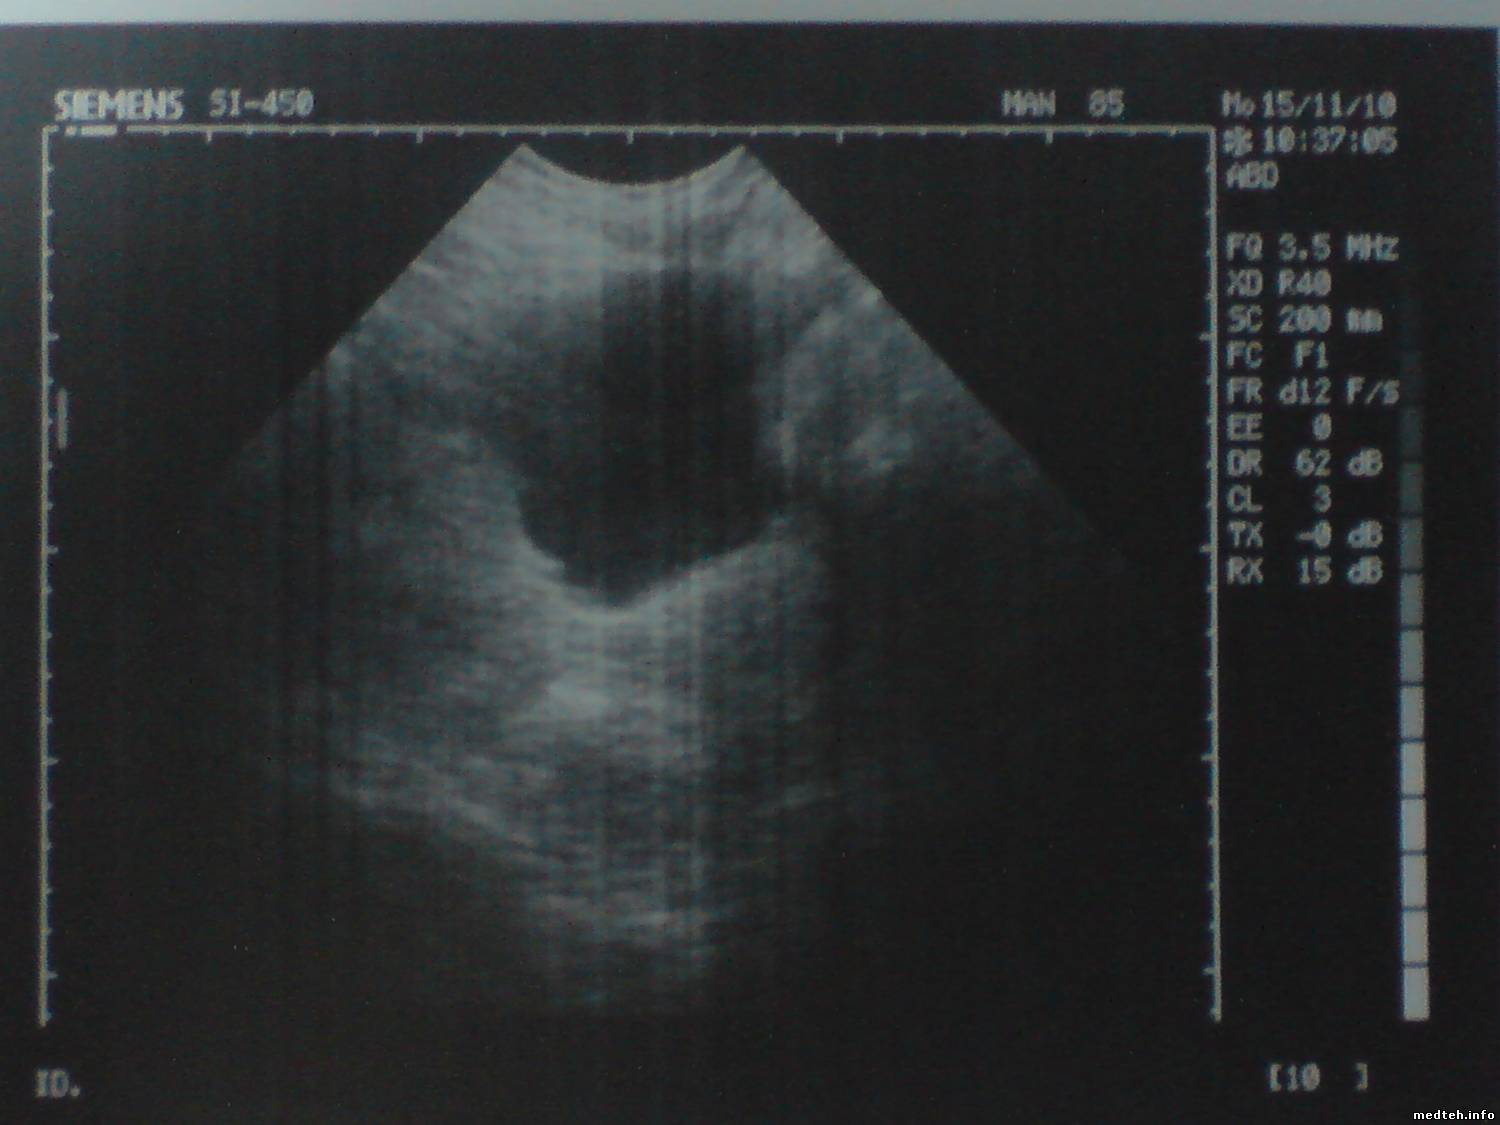

Проблема в том, что с настройками по умолчанию доктору не нравится изображение органов (не чёткие контура). Хотя аппарату 16 лет и может датчики уже не "тянут".

Может кто визуально определит и подскажет по фоткам чем можно поиграть в настройках.

Собственно говоря, в аппарате нечего настраивать. Корреляция, частота кадров (frame rate), пост-процесс. Если нет четкости ни на одном из датчиков,- проблемы с аппаратом. Если выбран адекватный пресет, картинка должна быть удовлетворительной. Сколько этих систем знаю, ни разу не слышал подобных жалоб. Единственный момент - картинка на линейке 7,5 МГЦ действительно не очень, ни в какое сравнение с нынешними системами не идет.

Датчиком которым смотрит щитовидку - изображение удволитворительное а

тут какраз и проблема.Посмотрите - есть снимки

На всех изображениях вертикальные размытые полосы, которые накладываются на полезный сигнал в видеоусилителе монитора - барахлит сам видеоусилитель или его питание. Плюс старый подсевший кинескоп и разрегулировка фокуса.

А вертикальные размытые полосы это на экране или только на снимках - дефект печати?

Похоже все-таки на печать :)

То, что я вижу,- это снимки снимков с принтера. И это дефекты самого принтера, а никак не аппарата, нужно фото именно с экрана, и с хорошим качеством, без фспышки. Тогда можно будет о чем-то говорить.

Размытость контуров может давать CL3 (корреляция). Попробуйте уменьшить.